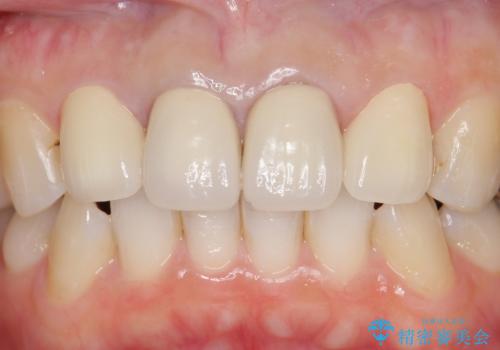

- 上顎の前から2番目の歯の古い樹脂をセラミックにしたいといらっしゃった方の症例です。

古い樹脂を除去後、オールセラミッククラウンによる補綴を行いました。

今回用いたオールセラミッククラウンはジルコニアフレームという白い素材の上にセラミックを盛っているため、審美性が非常に高いのが特徴です。

また、ジルコニアは人工ダイヤモンドの材料にも使われているほど高い強度を持っており、そのためオールセラミッククラウンは審美性だけでなく、奥歯やブリッジの補綴も可能とするクラウンです。